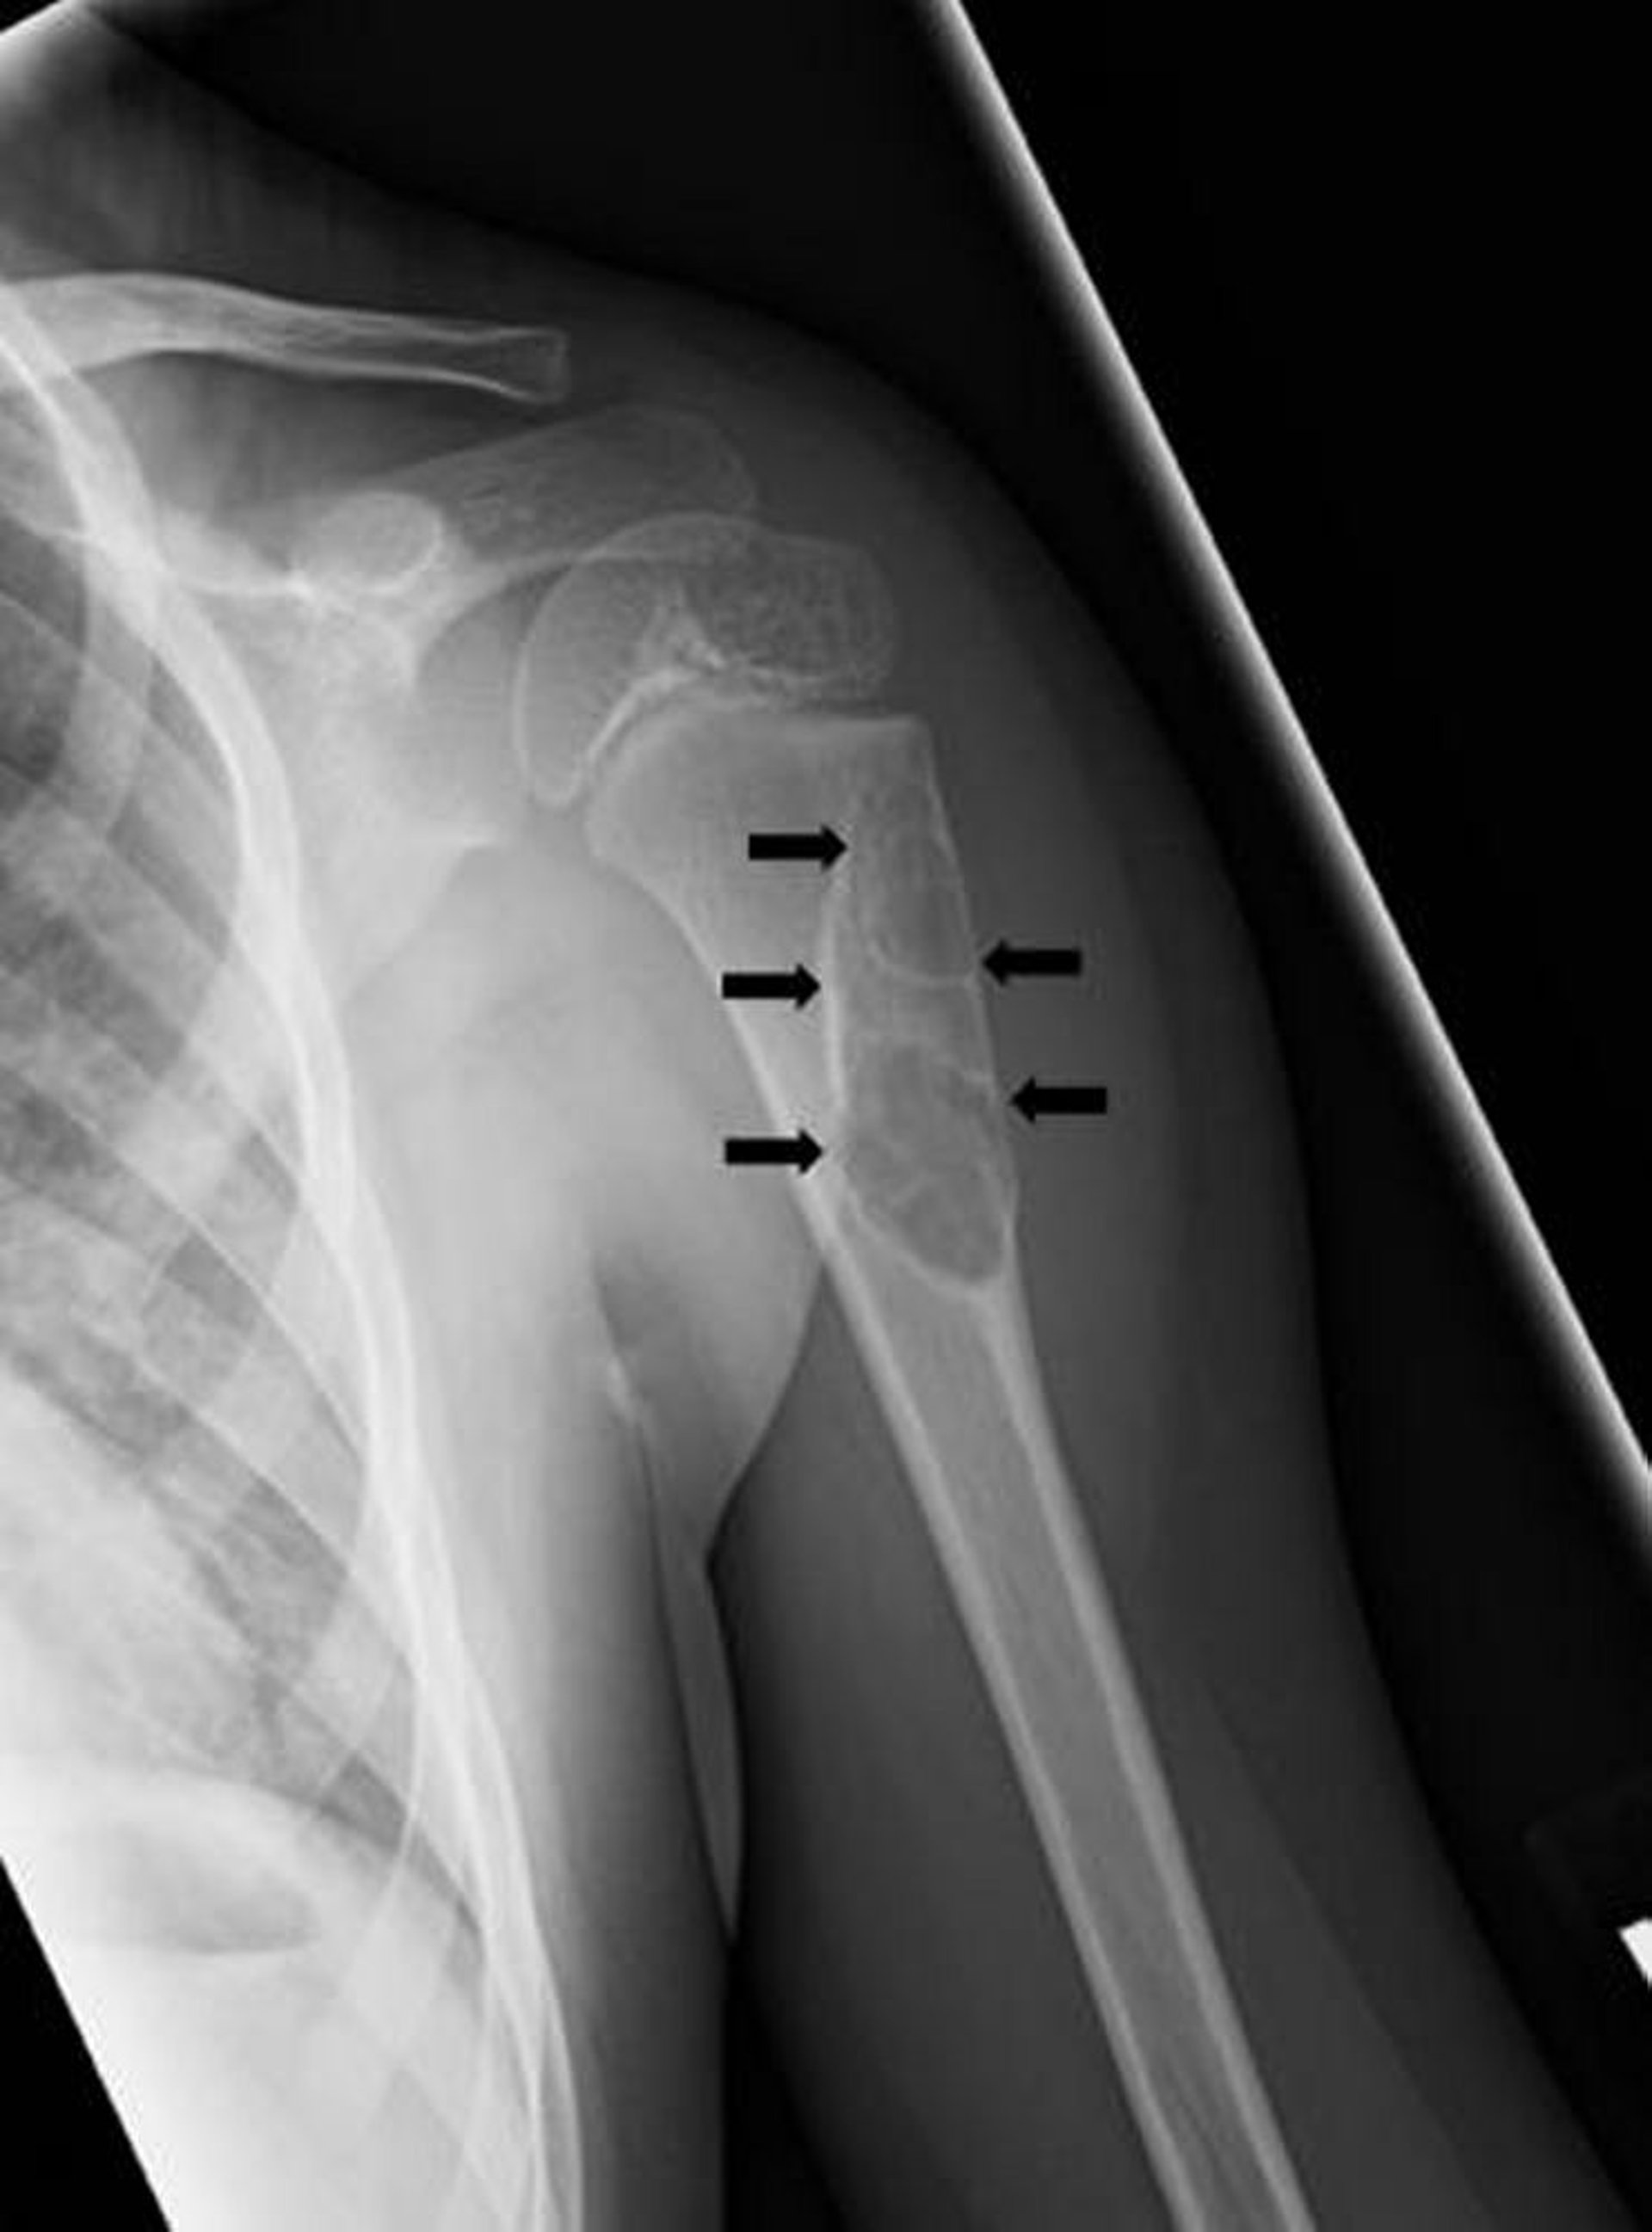

Cisti ossea semplice

Questa radiografia mostra una lesione cistica (frecce) dell'omero in un bambino coerente con una cisti ossea unicamerale.

Image courtesy of Michael J. Joyce, MD, and Hakan Ilaslan, MD.